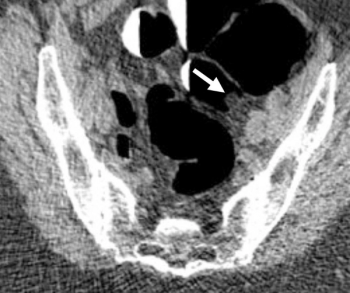

In a recent video interview, two radiology professors from the Yale School of Medicine discussed the impact of the iodinated contrast media (ICM) shortage and potential strategies, ranging from ICM dose reduction to possible deferment of non-urgent imaging, that may provide a viable path moving forward.